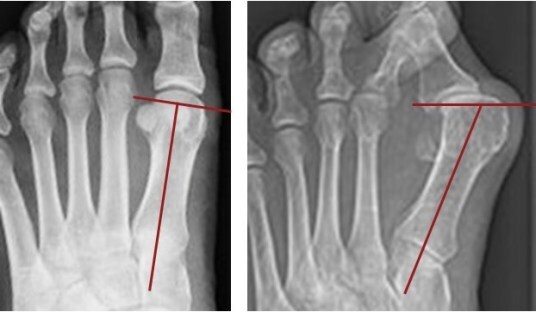

Left: normal alignment with the joint at the base of the big toe aligned perpendicular to the long axis of the foot. Right: a tilted joint surface indicates a bunion even if the skeleton is no longer intact.Using standard anthropological means, the investigators categorized each skeleton according to its age at death and its sex. They next scrutinized the foot bones for telltale signs of bunions. These findings include an angular shift of the joint surface at the big toe’s base along with bony erosions and altered ridging and lipping, which are characteristic findings of chronic joint malalignment. Finally, the researchers examined the entirety of each skeleton for healed fractures.